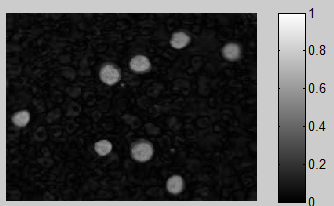

在这种特殊情况下,我会使用HSV。但与大多数颜色分割不同,我实际上会使用饱和通道来分割图像。细胞几乎相同的色调,所以使用色调通道将是非常困难的。

饱和巨大反差

现在我们有两个候选人代表饱和或绿色通道,我们问谁更容易处理?由于任何HSV工作涉及到我们转换RGB图像,我们可以忽略它,所以明确的选择是简单地使用RGB图像的绿色通道进行分割。